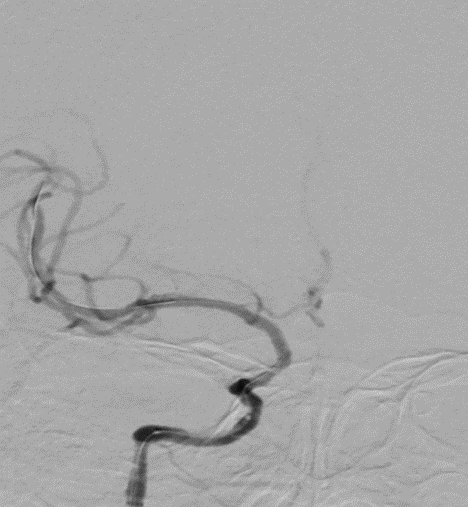

扩张后造影。

导丝怎么扩【载药时代 球扩天下】NOVA DES®颅内药物洗脱支架在颈内动脉颅内段重度狭窄的应用二例!_https://www.jmylbn.com_新闻资讯_第30张